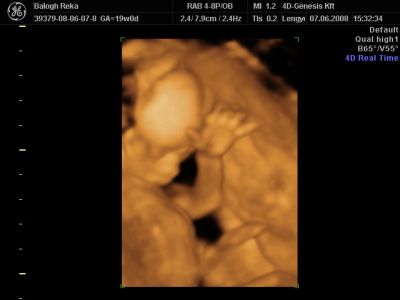

Huhh, hát annyira jó élmény volt, most tök boldog vagyok! Nagyon örülök, hogy mégis elmentem mégegyszer, mert sokat vacilláltam ám. A 4D Genesis egyszerűen szuper, mindenkinek nagyon nagyon tudom ajánlani, ezen belül is engem a Lengyel Györgyné Márti fogadott. Szuper ez a nő, akkora átéléssel és profizmussal csinálta az egész vizsgálatot! Mindent részletesen megnézett, megmutatott, elmagyarázott, nem sajnálta az időt. A felvétel gyönyörű lett, az egész baby nagyon szépen látszik, végig fent volt és mocorgott, hihetetlen aranyos volt, és nagyon szép!

Bemutatott párszor, ezek mind meg is vannak örökítve!

A dvd 35 perces, tehát ennyi volt az aktív része a dolognak, de összesen kb 1órát foglalkoznak veled, mert utána megmutatja sorban az összes fotót, ki lehet választani 1-et, és azt kinyomtatják. Itt akárhányszor vissza lehet nézegetni 1-1 képhez, hogy na melyik is legyen. Asszem 690-ért lehet extra képeket választani, de megjegyzem, hogy mi utána kinyomtattuk mind az 53-at a Media Marktban 55ft/db-ért. Tehát a 35perces dvd, genetikai vizsgálat, cd 53 képpel, és egy szép nyomtatott szines kép volt 12e ft. (1500 a cd, különben az alap ár 10.500 e nélkül) Nagyon nagyon meg vagyok elégedve vele, és tényleg komolyan mondom, hogy menjetek ti is oda!!! És még mindig kisláááány!

Na és a lényeg...jöjjenek a sztárfotók! Bocsi előre, 8 lesz és kicsit nagyok, de nem tudtam választani, azokat a bemutatásokat mind muszáj volt felraknom, tök vicces!